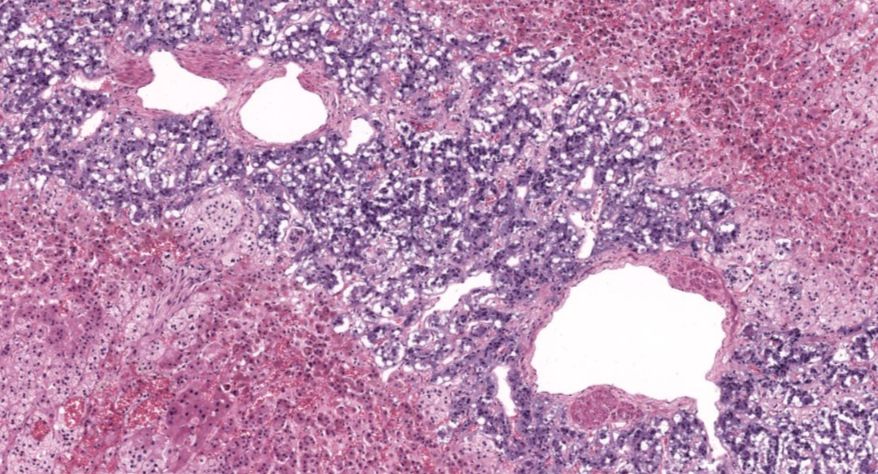

低倍镜观察:1. 被膜:由薄层结缔组织组成。2. 实质:由许多大小不等的滤泡构成。滤泡壁是单层立方上皮细胞,滤泡腔内充满粉红色匀质胶状物,滤泡之间的结缔组织内有丰富的血管。高倍镜观察:1. 滤泡:滤泡壁的单层滤泡上皮细胞一般呈低柱状或立方状,胞质着浅色,细胞核呈圆形。滤泡腔内充满了粉红色匀质胶质。2. 滤泡旁细胞:体积较大,呈圆形或椭圆形;细胞核较大,呈圆形,着色较浅,细胞质染色也较浅。细胞或嵌在滤泡壁上或成团分布于滤泡之间。3. 间质:由结缔组织组成。位于滤泡之间。其中含有丰富的毛细血管及三五成群的滤泡旁细胞。

1.全景图

![]()

2.滤泡

3.滤泡上皮细胞

4.胶质

5.滤泡旁细胞1

7.滤泡旁细胞2